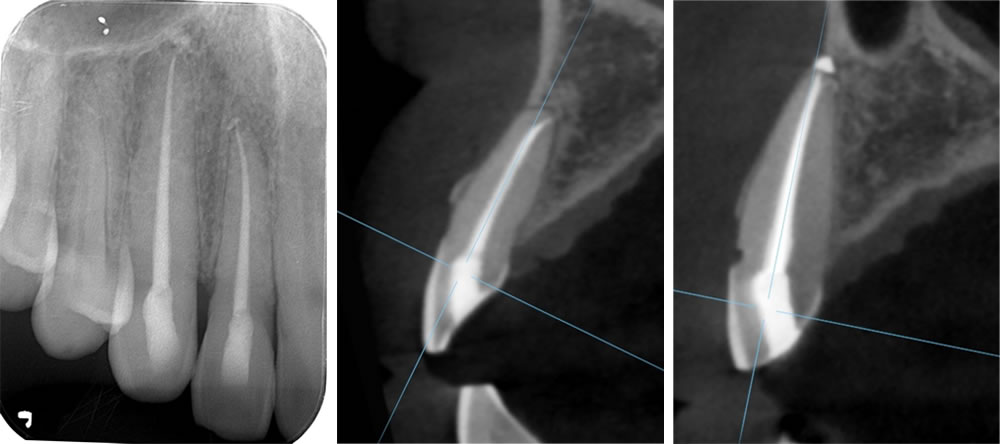

初診時のレントゲン画像・CT画像

初診時のレントゲン写真とCT画像です。犬歯に至っては、大きく外に飛び出ていることが確認できます。

こちらはレントゲンとCT画像になります。受傷後は骨から大きく飛び出ていた歯牙は正しい位置にあります。また、正常な歯根膜の確認もでき、経過良好です。